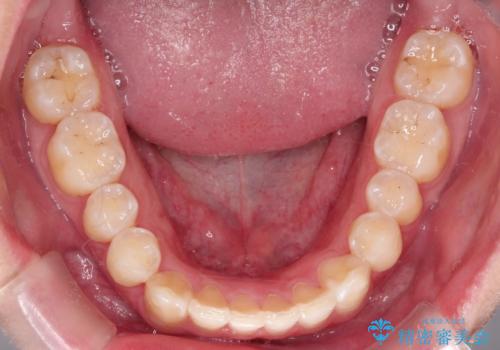

- 前歯がガタガタ、下の犬歯が飛び出ているのを主訴に来院されました。

下の奥歯を後方へ移動させてスペースを確保して、前歯を並べる計画としました。